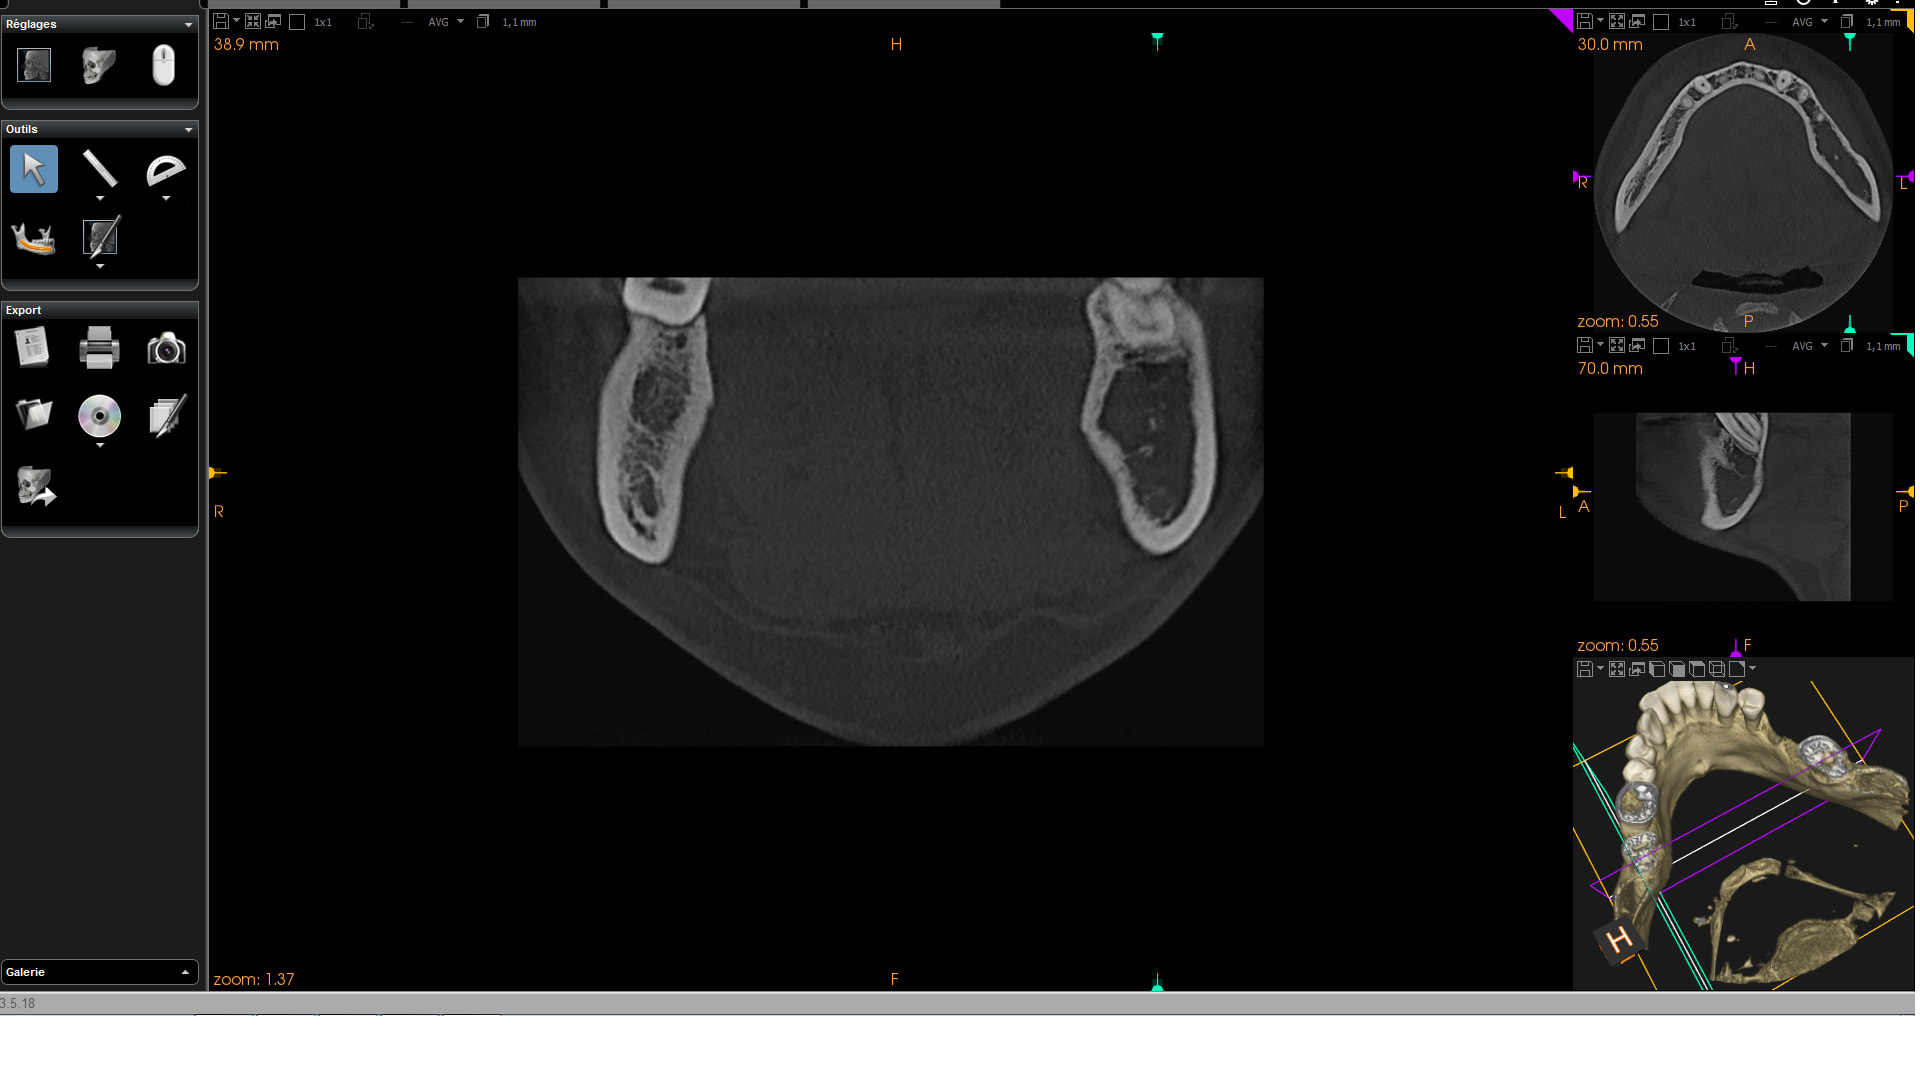

le patient a eu bobo en secteur 3, genre infectieux, bien gonflé j'ai rien trouvé à la rétro à la rétro à part une densité bizarre après les apex. La gencive fait une blague ? bof j'y crois moyen.

je fait un CBCT et je trouve ce genre d'image.

Ostéomyélite phase chronique ?